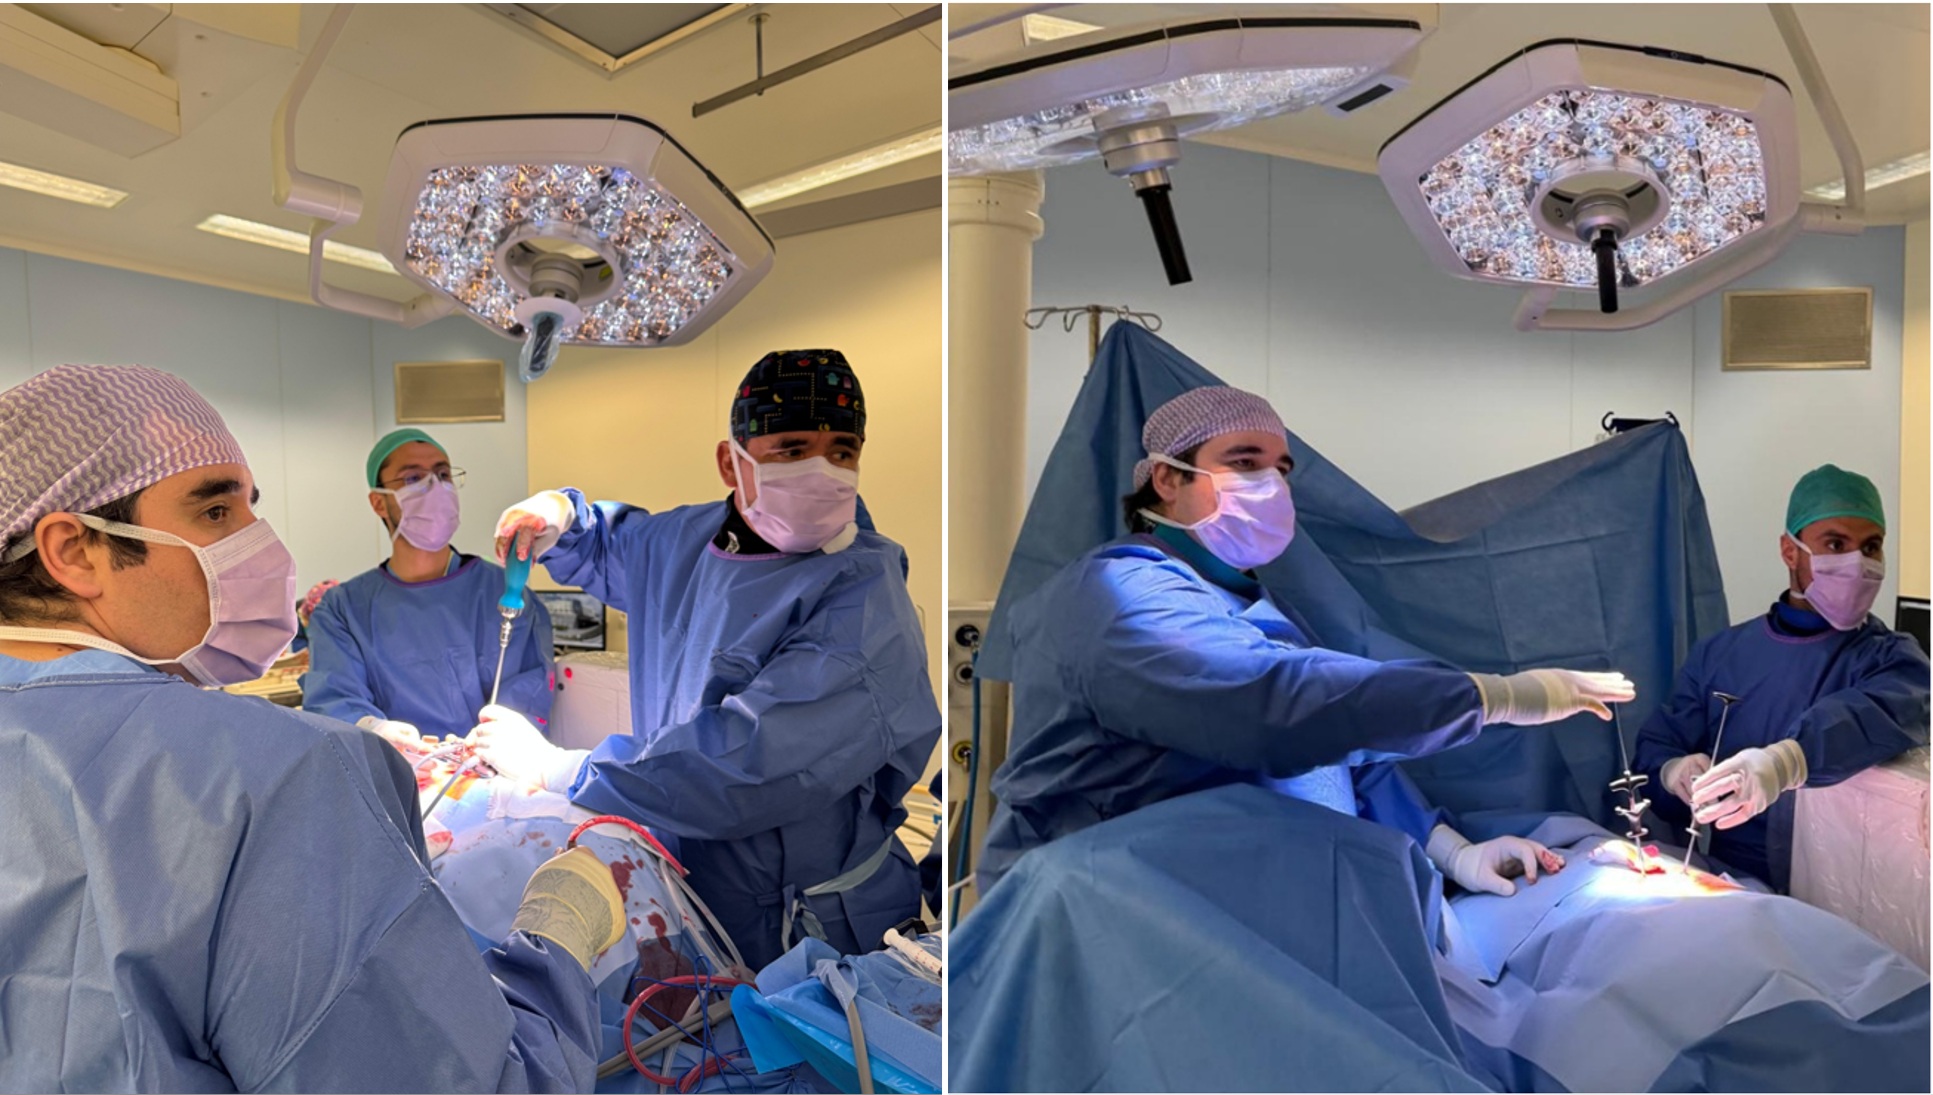

Manejo médico y qurúrgico de múltiples patologías neuroquirúrgicas (cerebro y columna)

Neurocirujano formado en la Universidad de Santiago de Chile (USACH), con especial cercanía a la patología de columna y al neurotrauma. Enfoque centrado en el bienestar integral del paciente, combinando criterios clínicos, neuroimagen y práctica basada en evidencia.

En esa linea realicé una estadía de perfeccionamiento de 2 meses en la unidad de raquis del Hospital clinic de Barcelona y actualmente me encuentro cursando una nueva estadía de perfeccionamiento de un año en la unidad de columna del Hospital Dr. Sótero del Río